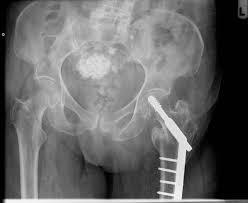

What is abnormal about this radiograph? What is the most likely comorbidity?

This patient manifests two tracklike calcifications symmetrically on each side of the bladder that end in the urethra – the vas deferens! This occurs much more commonly and earlier in diabetics than as a natural degenerative process.